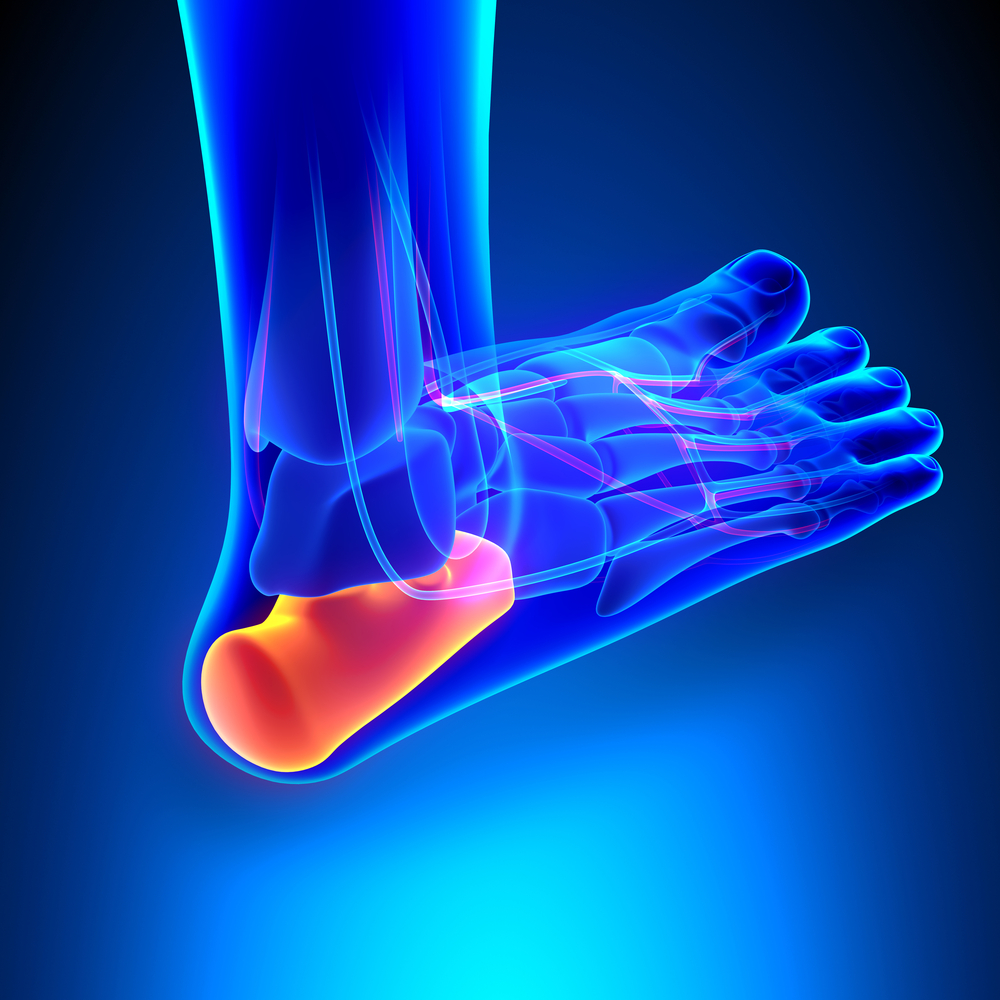

Ankle Bone Spur

Ankle Sprain

Ankle Fracture

Ankle Syndesmosis Ligament Injury

Ankle Dislocation

Tarsal Tunnel Syndrome

Ankle Instability

Posterior Tibial Tendon Dysfunction

Metatarsalgia

Bunion Or Hallux Valgus